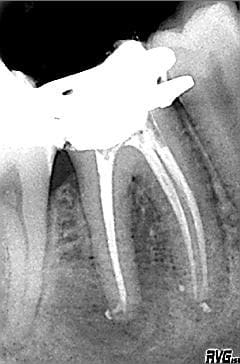

Suite et fin de mon cas, après avis au gynéco et temporisation d'une séance à l'hydroxyde de Ca j'ai obturé ma 46 aujourd'hui sous tablier de plomb.

J'ai des dents à extraire également et la gynéco m'a donné le feu vert pour les faire.

Ci joint la cause de toutes mes inquiétudes ^^